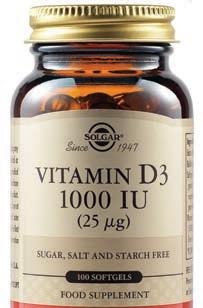

LIPOSOMAL VITAMIN C